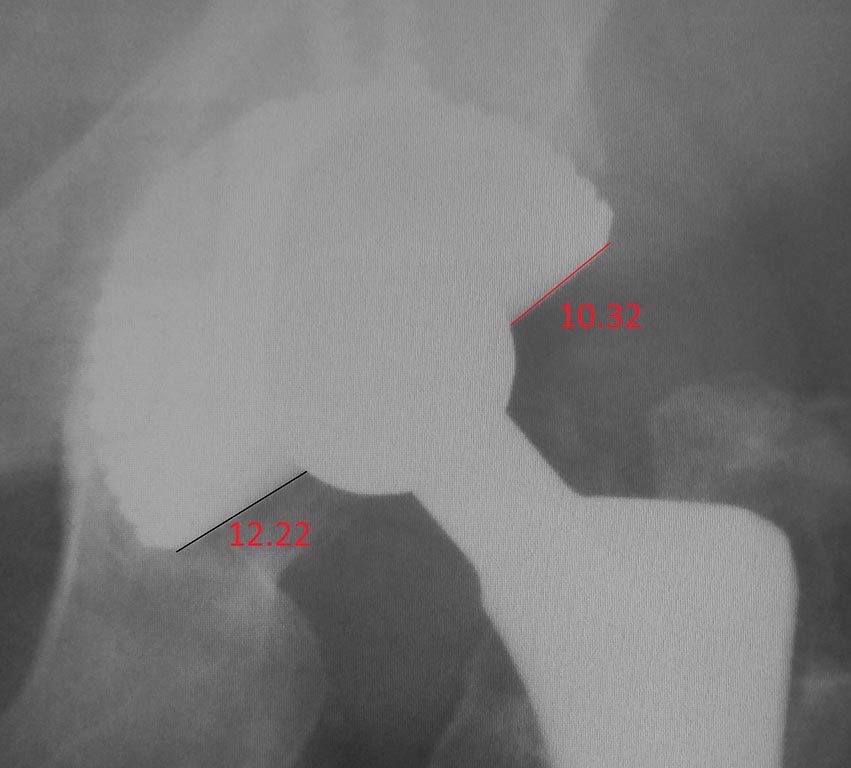

Приблизил и обрезал отдельно ацетабулярный компонент. Видно, что головка не по центру ацетабулярного компонента, а смещена кверху

Добрый день. Децентрация очевидна, ее померить можно во многих редакторах (единице в приложенном мною файле условные).

Что делать сейчас? Боюсь, консенсуса нет.

Критерии, какой износ вкладыша в мм можно считать показанием к ревизии, мне не известны. Обычно считается, что показание - остеолиз, который возникает как следствие полиэтиленового дебриса.

Причем есть четкая тенденция ревизовать при остеолизе, не дожидаясь нестабильности - дальше будет хуже и тяжелее, так как остеолизный дефект часто интраоперационно гораздо объемнее, чем могло казаться по Рг.

При этом чем раньше принято решение, тем увереннее можно обойтись благодарной операцией замены вкладыша без замены чашки.

В вашем случае я бы искал остеолиз, который в ранних стадиях на представленных некачественных рентгенах искать бессмвысленно, и от критерия есть остеолиз или нет бы отталкивался.